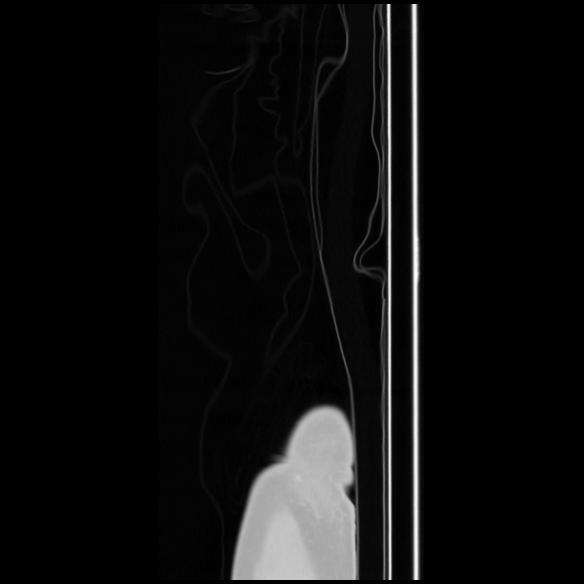

7 CUERPO,CE,Sagittal,3.000,CUERPO,Sagittal,